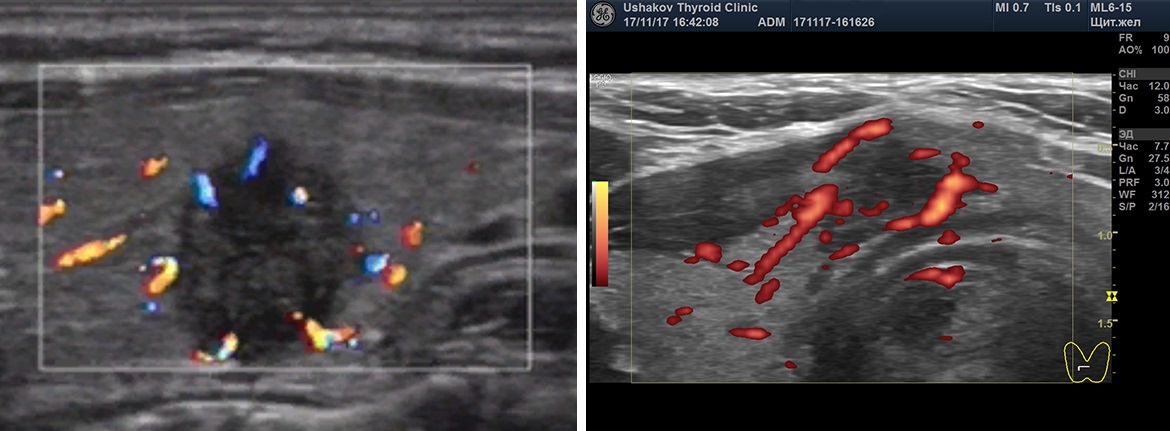

Рисунок. 7. Неупорядоченный кровоток узлов щитовидной железы.

Клиника щитовидной железы доктора А.В. Ушакова ввела такой признак оценки кровотока как его «упорядоченность». Под упорядоченностью кровотока узла понимается расположение сосудов в соответствии с естественным сегментарным устройством ткани узла. Упорядоченность кровотока узлов может быть в разной степени выражена. Беспорядочный кровоток (т.е. независимо от сегментов) относится к важному признаку злокачественности ткани узла. Такое беспорядочное расположение сосудов возникает при неравномерном и несегментированном прорастании сосудов вместе с образованием раковой ткани.